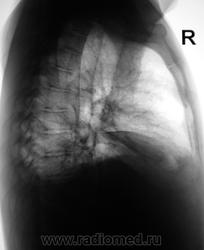

Динамика через 3 дня.

За три дня, следовательно, 0,5 л жидкости слева ушло.....а справа резко прибыло ...как будто только диафрагмы, но без значительного прибавления жидкости...Интересно....печень же за три дня так не увеличиться...

Поскольку такой внезапный парез диафрагмы маловероятен...смею предположить наличие базального плеврита справа...он же - диафрагмальный плеврит. Здорово бы было посмотреть на УЗИ - за три секунды решили бы проблему.